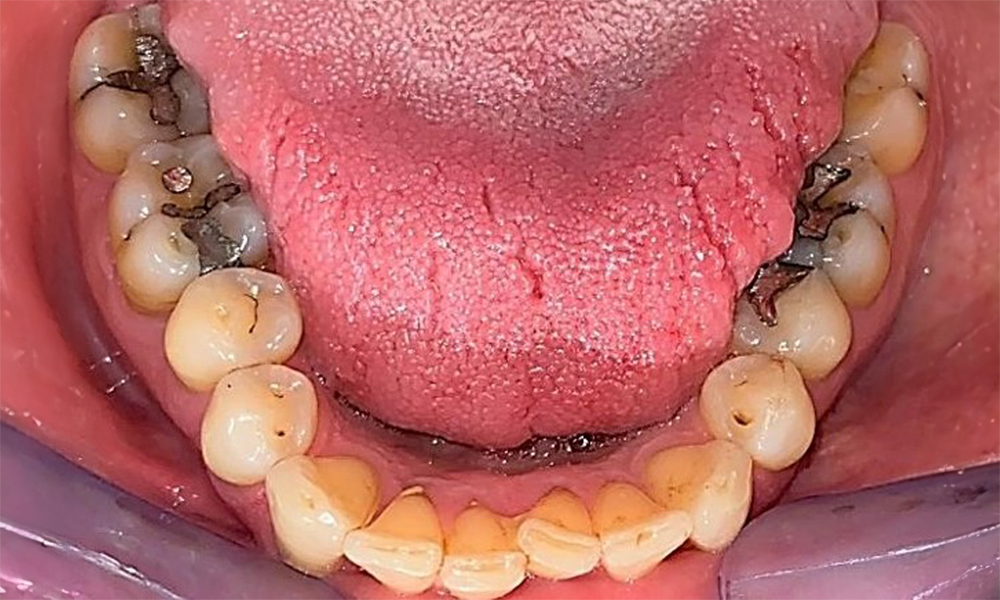

Pacientul prezintă dentiție completă cu 28 de dinți, care include obturații din amalgam și compozit pe molari și premolari. Există un spațiu marginal clinic vizibil la 14. Molarul 27 prezintă un inlay din aur adecvat. Se observă, de asemenea, atriții și abrazii generalizate. (Fig. 2, Fig. 3, Fig. 4, Fig. 5, Fig. 6)

Pacientul prezintă boală parodontală în stadiul II, gradul B (5). Profunzimile clinice de sondare observate, între 1 și 3 mm, se încadrează în limitele fiziologice. Localizat, s-au observat profunzimi de 5 mm, la nivel meziopalatin, atât pe 17, cât și pe 27. Se constată recesiuni generalizate de 1-3 mm, cu pierderi parțiale ale papilelor interdentare (Fig. 2, Fig. 3, Fig. 4)